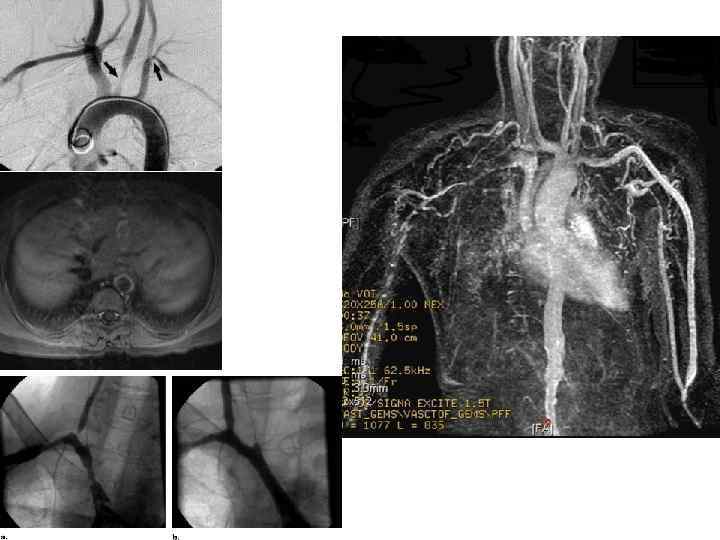

АОРТОАРТЕРИИТ ТАКАЯСУ 1. РАЗНИЦА НАПОЛНЕНИЯ ПУЛЬСА И АД НА РУКАХ 2. ЧАЩЕ СТРАДАЮТ ЖЕНЩИНЫ СРЕДНЕГО ВОЗРАСТА 3. ПРИЗНАКИ ВОСПАЛЕНИЯ (ПОВЫШЕНИЕ СОЭ, ЦРБ) 4. ДОППЛЕРОМЕТРИЯ ДЕМОНСТРИРУЕТ РАЗНИЦУ ОБЪЕМНОГО КРОВОТОКА

АОРТОАРТЕРИИТ ТАКАЯСУ 1. РАЗНИЦА НАПОЛНЕНИЯ ПУЛЬСА И АД НА РУКАХ 2. ЧАЩЕ СТРАДАЮТ ЖЕНЩИНЫ СРЕДНЕГО ВОЗРАСТА 3. ПРИЗНАКИ ВОСПАЛЕНИЯ (ПОВЫШЕНИЕ СОЭ, ЦРБ) 4. ДОППЛЕРОМЕТРИЯ ДЕМОНСТРИРУЕТ РАЗНИЦУ ОБЪЕМНОГО КРОВОТОКА